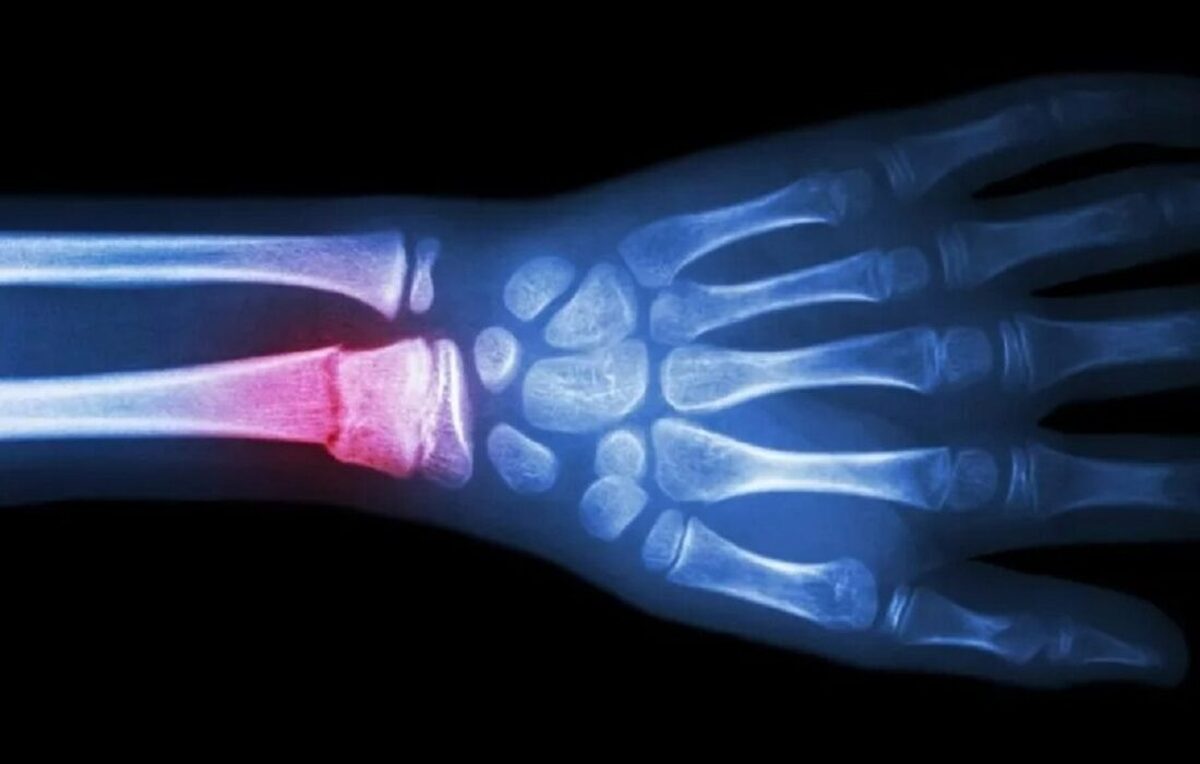

ترمیم استخوان شکسته با یک تفنگ درمانی!؛ گزینه ای سریع تر و مقرون به صرفه تر برای ترمیم

به گزارش برنا، پیوند فلز و ایمپلنتهای مبتنی بر تیتانیوم همچنان جزء روشهای استاندارد تثبیت شکستگیهای شدید استخوان به شمار میرود، اما تولید آنها گران است و سفارشیسازی آنها برای هر بیمار دشوار است. این در حالی است که اگرچه چاپ سهبعدی دری را به روی راهحلهای شخصیسازیشدهتر باز کرده است، اما هنوز به زمان و منابع قابل توجهی نیاز دارد. به همین دلیل محققان دانشگاه سونگ کیون کوان در کره جنوبی، در جستجوی گزینهای سریعتر و مقرونبهصرفهتر، به توسعه روشی پرداختند که میتواند ایمپلنتهای استخوانی مخصوص بیمار را بدون هزینههای بالا یا سرعت کم روشهای سنتی ایجاد کند.

به نقل از آیای، تفنگ ترمیم استخوان آنها شبیه یک چاپگر سهبعدی دستی است، اما به جای پلاستیک، داربستهای پلیمری زیستتخریبپذیر را مستقیما در طول عمل جراحی روی استخوانهای شکسته اعمال میکند. این دستگاه «گلولههای» پلیمری مخصوص را در دمای ایمن ۶۰ درجه سانتیگراد ذوب میکند، دمایی که به اندازه کافی سرد است تا از بافت اطراف محافظت کند و در عین حال یک چارچوب مخصوص برای رشد استخوان جدید تشکیل دهد.

ساخت یک چسب حرارتی که بتواند استخوانها را ترمیم کند، برای گروه لی دشوار بود. چسب حرارتی استاندارد در دمای بیش از ۱۰۰ درجه سانتیگراد ذوب میشود که دمایی بسیار بالا برای بافت زنده است. این ماده همچنین باید با استحکامی مشابه استخوان طبیعی سخت میشد و به تدریج تجزیه میشد تا استخوان جدید بتواند جایگزین آن شود. این سه چالش یعنی دمای ایمن، استحکام مشابه استخوان و تجزیه زیستی کنترلشده، راهنمای طراحی داربست ترمیم استخوان آنها بود.

همانطور که لی توضیح میدهد، گروهش قبل از یافتن ترکیب مناسب، چندین مخلوط را آزمایش کردند. آنها پلیکاپرولاکتون، یک ترموپلاستیک مورد تایید سازمان غذا و دارو را که در عرض چند ماه به طور ایمن در بدن تجزیه میشود، با هیدروکسی آپاتیت که یک ماده معدنی است که به رشد استخوان جدید کمک میکند، ترکیب کردند. پس از تنظیم نسبتها، آنها به ترکیبی دست یافتند که در دمای ملایم ۶۰ درجه سانتیگراد ذوب میشود، به طور ایمن به استخوان متصل میشود، در طول بهبودی قوی میماند و به تدریج با جایگزینی بافت طبیعی، تجزیه میشود.